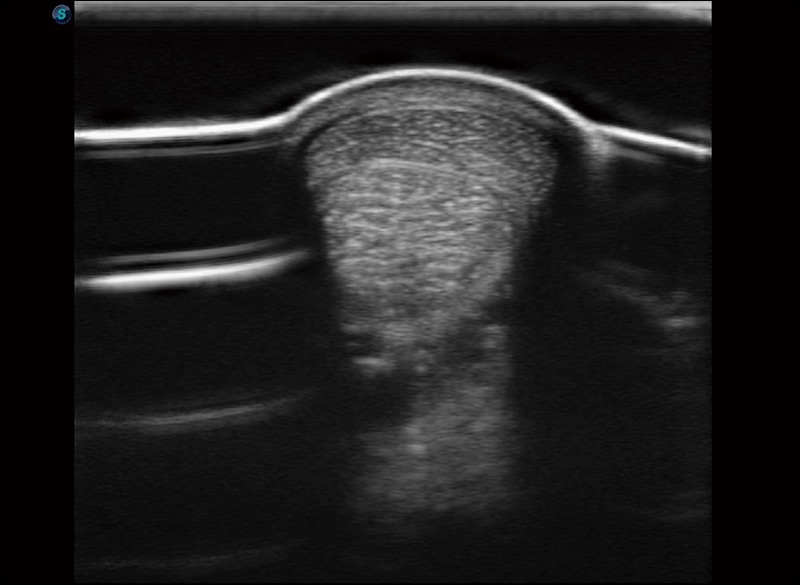

任意波束合成技术

在不牺牲时间分辨率的情况下提供出色的图像

空间复合成像

优化不同角度的图像